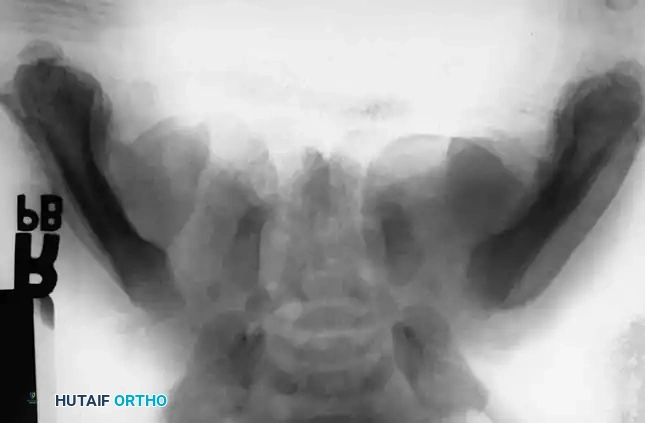

Every jurisdiction requires physicians to act as mandated reporters of suspected child abuse. Definite knowledge or a confirmed specific diagnosis is not required to make a report; reasonable clinical suspicion is sufficient.

Surgical Warning: It is a tragic reality that few fractures in this demographic strictly require open reduction and internal fixation from a purely biomechanical standpoint. However, admission for surgical management or observation often serves a dual purpose: it provides optimal orthopedic care while simultaneously sheltering the abused child from their abusers until child protective services can intervene.

Regardless of the treatment modality chosen, the orthopedic surgeon's paramount duty is to protect the child. The surgeon must inform the parents or guardians of their legal and ethical responsibility to report the injuries to the appropriate authorities.

Image